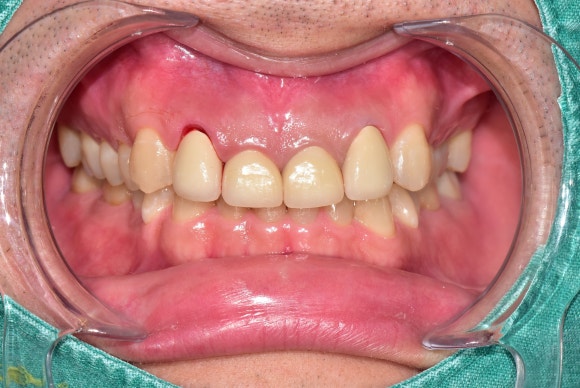

20250502

치료를 시작한지 두 달 정도 경과했습니다.

원하는 치아량은 이미 확보했습니다.

치아를 새로운 위치에 고정시키기 위해

유지기간*을 가지고 다시 내원하셨습니다.

- 치아가 새로운 위치에 고정되려면

가만히 지켜봐주는 기간이 필요합니다.

새롭게 신경치료를 하고

뿌리와 머리를 튼튼하게 지지해줄

세라믹 기둥도 세워넣었습니다.

그리고 마지막으로 크라운을 제작했습니다.

<치료 후>

새로운 크라운을 만드는 김에

평소에 신경쓰였던 치아 높이 비대칭도

함께 해결하였습니다.

예쁘고 튼튼한 새 이가 생기신 것을 축하드립니다.